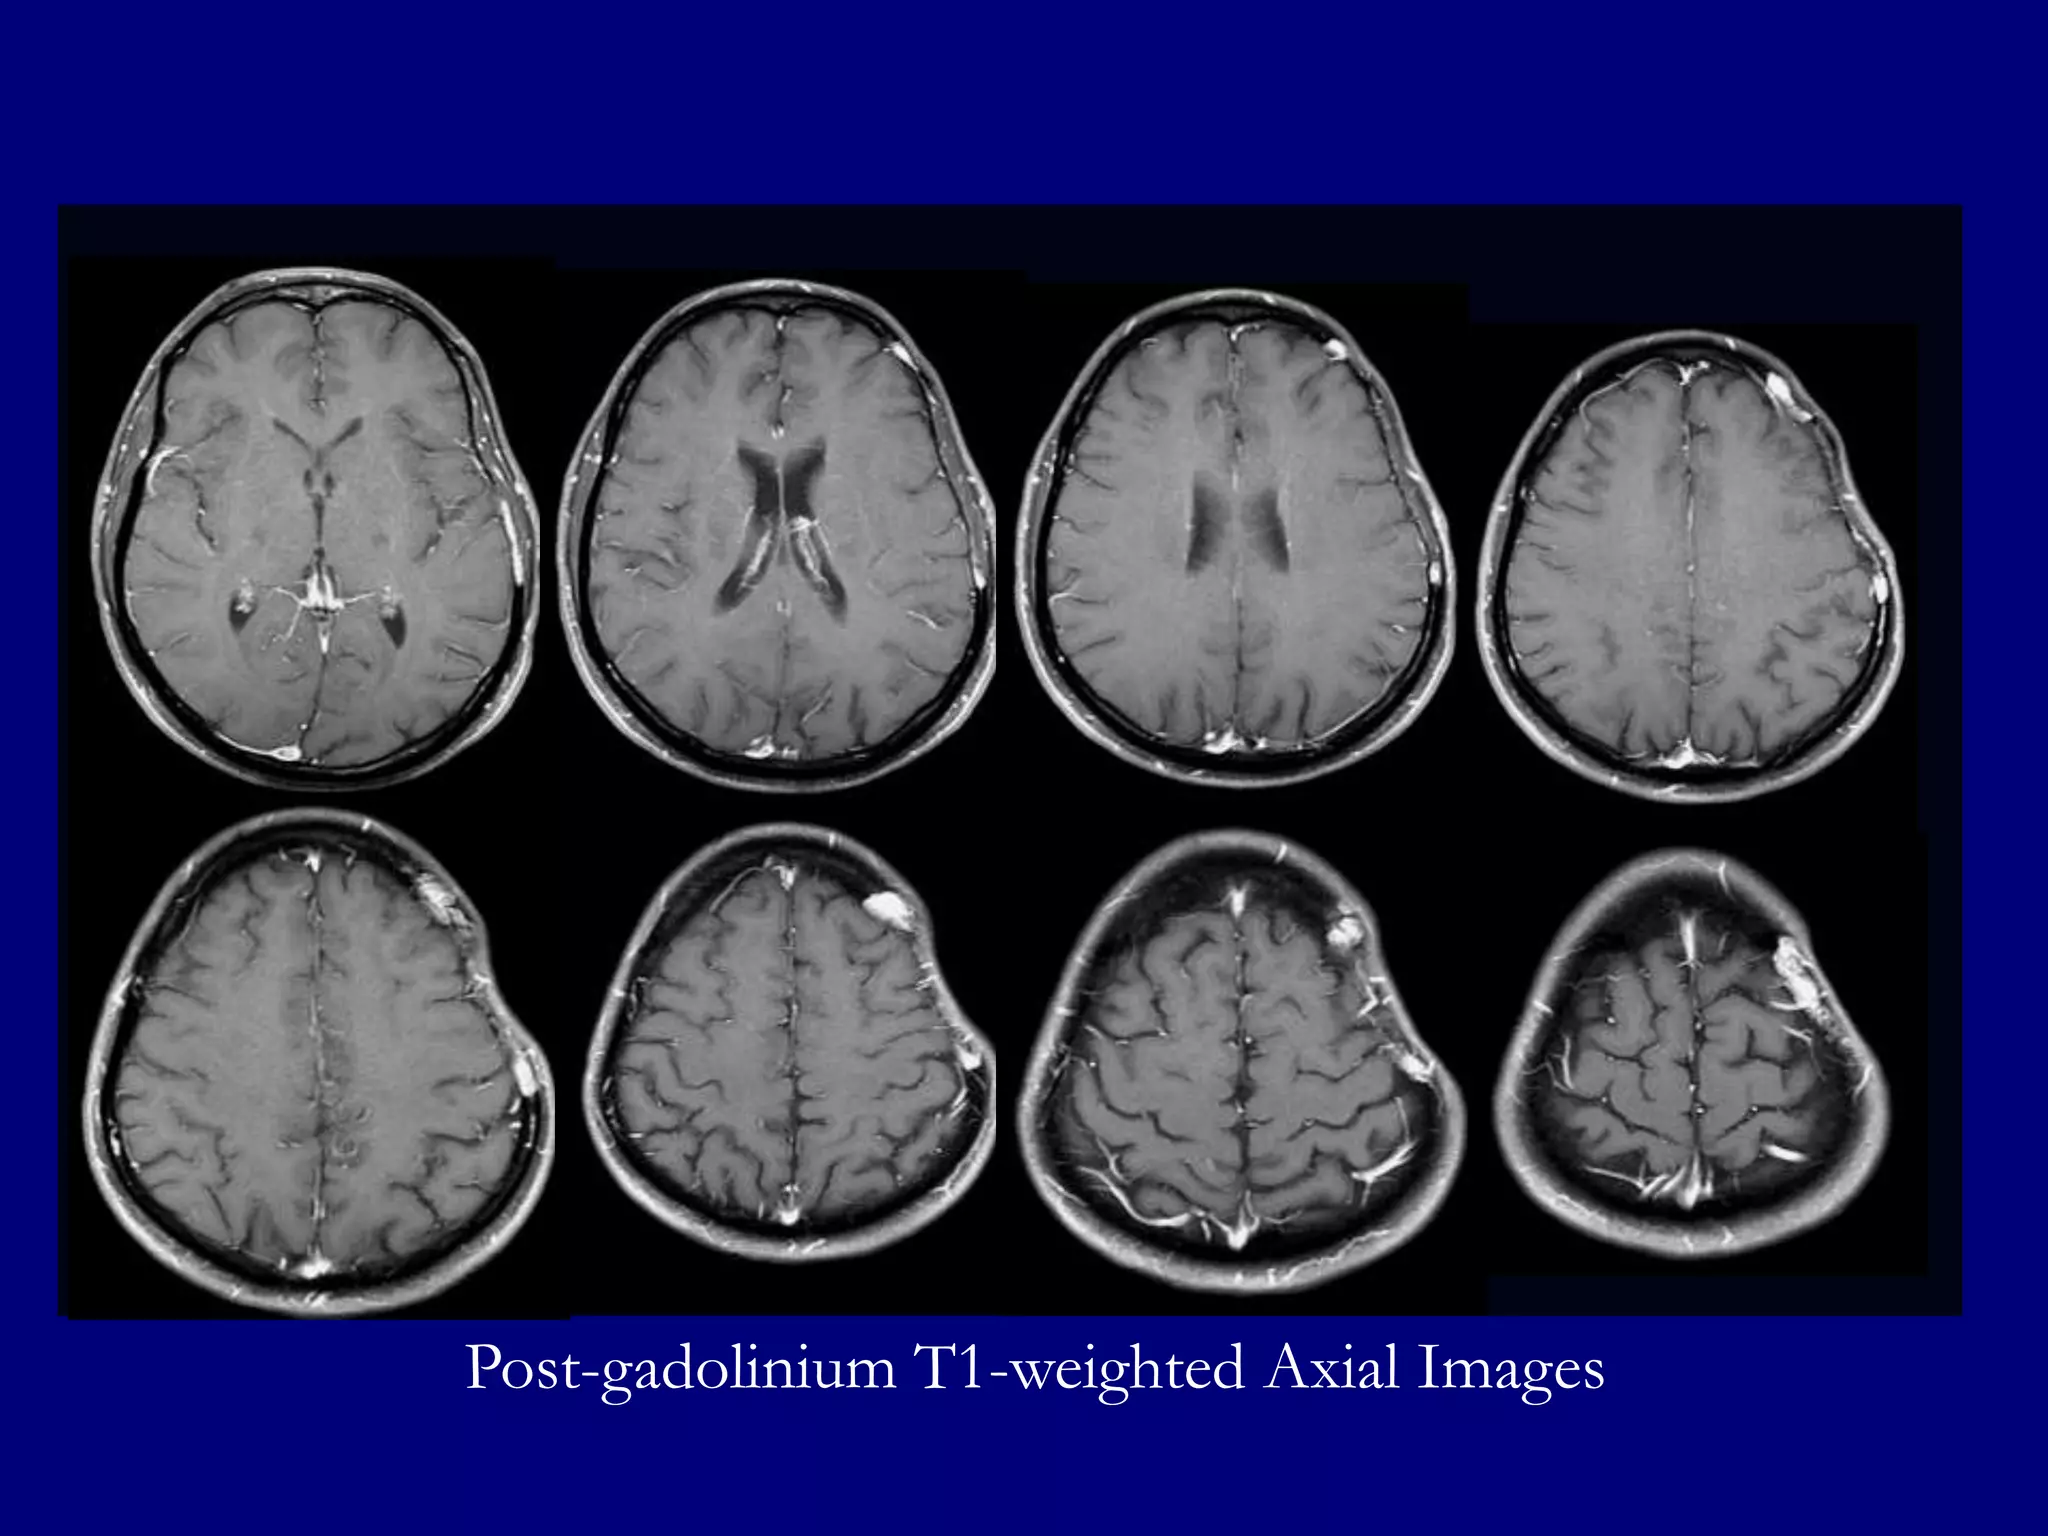

Post-gadolinium T1-weighted Axial Images